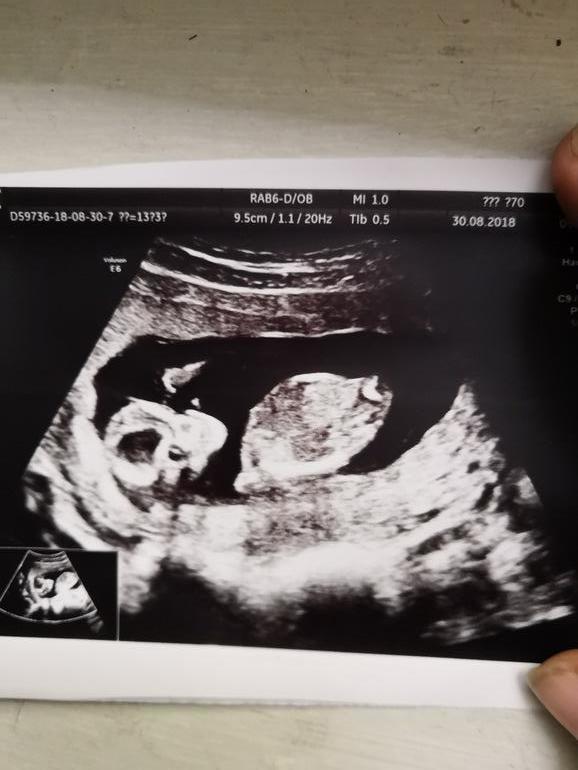

Пол тогда тоже не сказала, вообще не видно сказала (хоть особой разницы небыло,но было интересно), недели через две я решила повторить узи,и пол уточнить и про шейку разузнать. Шейка такая же была ну 30-32 сказала узистка,и тонус был,пол сразу увидели

надеюсь других сюрпризов не будет 😂 уже всем сказали мальчик да и сами настроились уже на мальчика,и вот еще одна фоточка